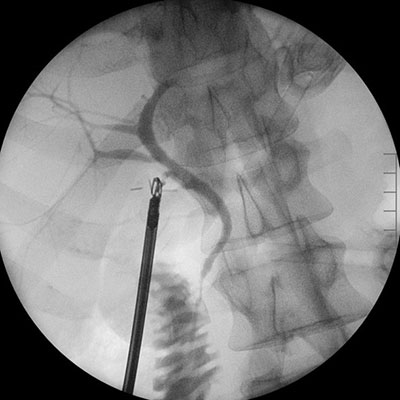

An intraoperative cholangiogram, an X-ray of the bile ducts, is often performed during the surgery to check for any stones that may have moved into the bile duct. If stones are found within the bile ducts, they are removed either during the surgery using a small basket or, in most cases, with a follow-up procedure called an ERCP (Endoscopic Retrograde CholangioPancreatography) the next day.

Cholecystectomy is considered a safe and effective procedure, with a complication rate of less than 1%. However, as with any surgery, there are general risks such as bleeding, infection, blood clots, and reactions to anaesthesia. Specific risks associated with gallbladder removal include bile leaks or injury to the bile duct system. If these complications occur, they are treated by draining any accumulated bile and performing an ERCP to stop the leakage.